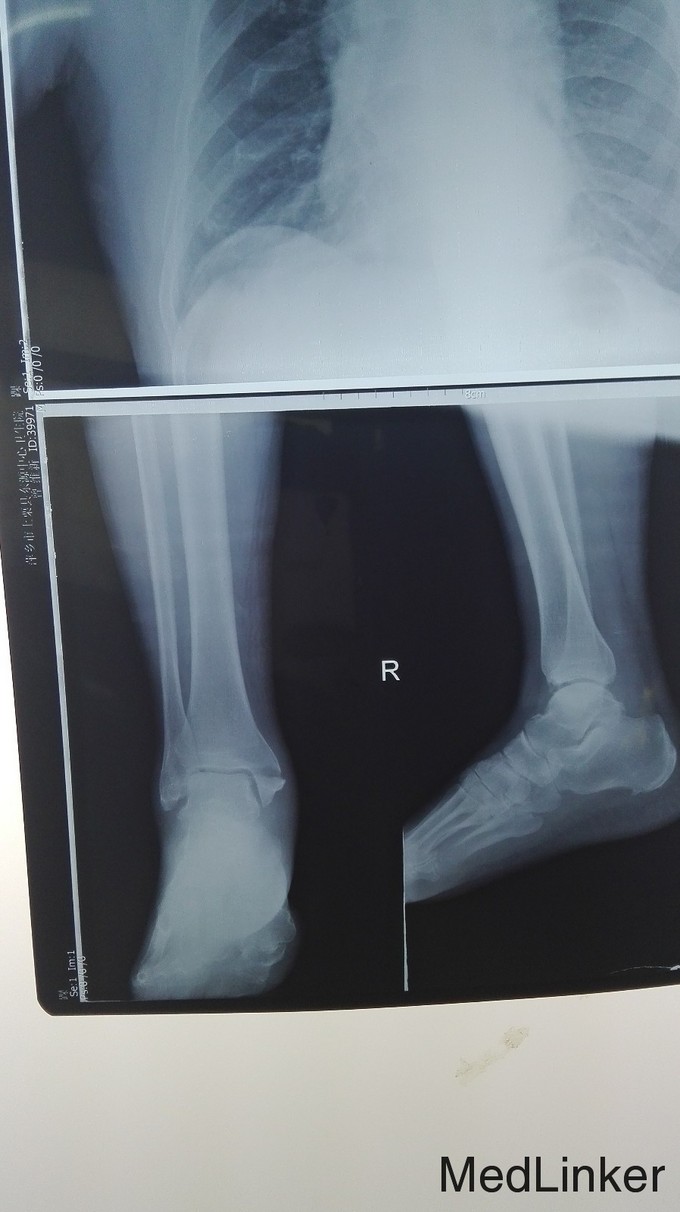

右内踝撕脱骨折

患者缘于2015年10月12号中午在家托板车摔伤致全身多处疼痛,当时未做特殊处理,于2015年10月13日呼叫我院救护车护送来我院,门诊查体并X线 片及自带CT示后拟:1.右内踝撕脱骨折,2右外踝骨折。收入本科住院治疗。

右内踝撕脱骨折。 行内踝骨折切开复位加内固定术。